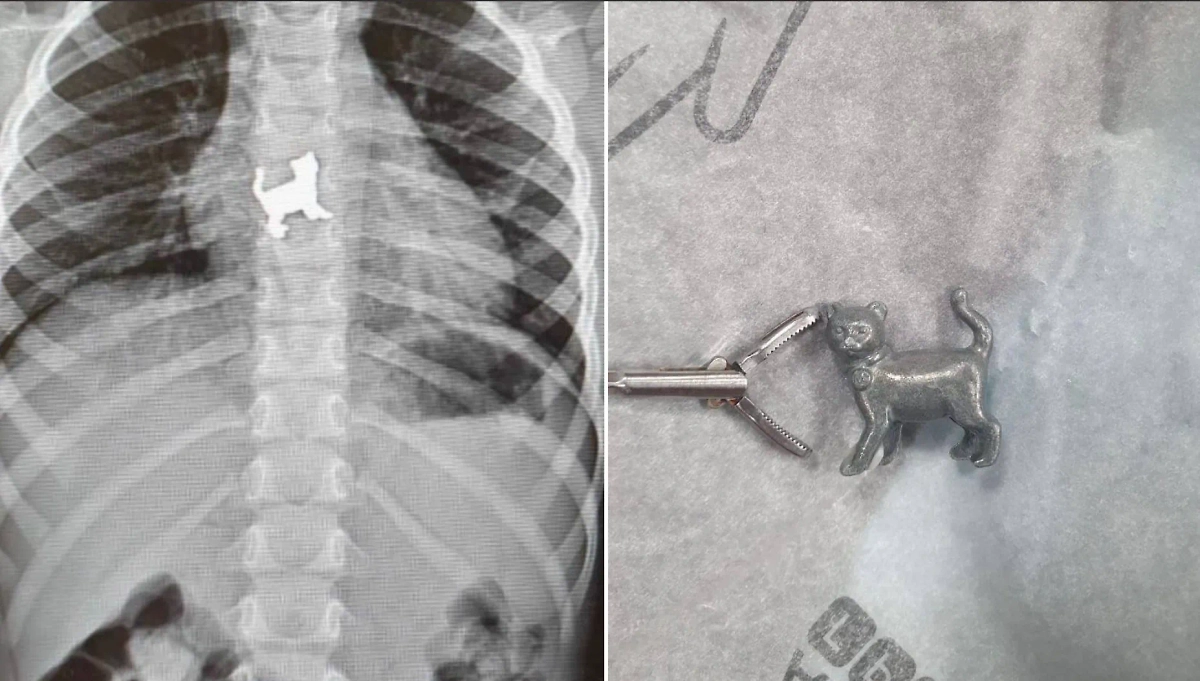

В Уфе трёхлетняя девочка во время игры проглотила металлическую игрушку в форме котёнка, с болями в груди её доставили в больницу. Об этом рассказал министр здравоохранения Башкирии Айрат Рахматуллин.

Ребёнка спасло то, что родители были дома и вовремя заметили, что дочь что-то взяла в рот. Металлический предмет вызвал сильные спазмы в животе, а также резкие боли в грудной клетке. Семья тут же отвезла малышку в Республиканскую детскую клиническую больницу.

"Пациентку госпитализировали в хирургическое отделение, где провели ригидную эзофагоскопию и удалили инородное тело", — пояснил Рахматуллин. Сейчас с девочкой всё в порядке.